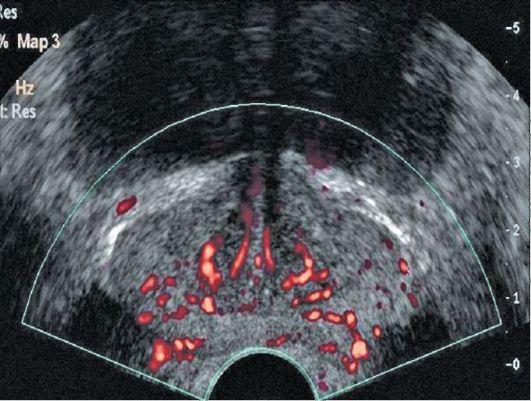

За статистикою, 63% українських чоловіків старше 35-40 років мають проблеми з сечовипусканням і потенцією, які є основними симптомами запущеного простатиту. У решти - простата також не в порядку, але до характерних симптомів поки не дійшла. За тією ж статистикою медиків, патологічні процеси в простаті (в тій чи іншій мірі) спостерігаються у 98% українських чоловіків старше 35-40 років.

Сам по собі простатит - це пряма дорога спочатку до аденоми простати, а потім до імпотенції та раку. Проблема ускладнюється ще тим, що лікування від простатиту складне і тривале. Необхідно приймати велику кількість антибіотиків і пройти курс масажу простати (лікар через анальний отвір пальцем масажує пацієнтові простату щодня протягом 2 тижнів). Але навіть при успішному лікуванні простатит в 87% випадків повертається знову протягом 1 року.